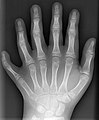

Historische X-Ray Glasplatte 24 × 30 cm – vermutlich Erster Weltkrieg – Torso einer Krankenschwester aus Deutschland -

Eine moderne Aufnahme einer linken Hand mit 6 Fingern (Polydaktylie) -